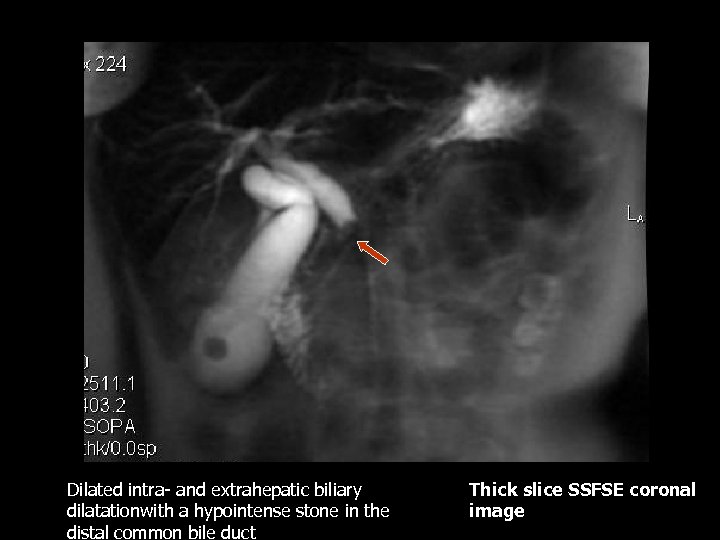

Dilated intra- and extrahepatic biliary dilatationwith a hypointense stone in the distal common bile duct Thick slice SSFSE coronal image

Choledocholithiasis • Heavily T 2 weighted images can show filling defects within the CBD and secondary signs such as CBD and intrahepatic biliary dilatation(2). • Treatment: cholecystectomy • MRCP images – heavily T 2 weighted images in a 3 D display can demonstrate filling defects within the CBD as well as secondary signs such as biliary system dilatation.